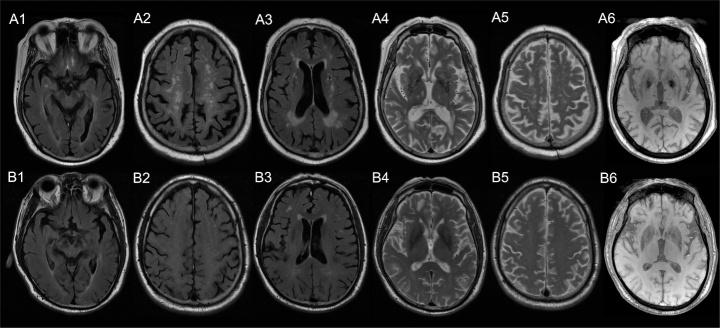

Inferior frontal sulcal hyperintensity (IFSH) on FLAIR sequence may indicate elevated cerebrospinal fluid (CSF) wastes. The objective of this study was to investigate its association with the clearance function of putative meningeal lymphatic vessels (mLVs). We included patients who underwent FLAIR sequence and dynamic contrast MRI with intrathecal administration of contrast agent. The visibility of IFSH was quantitatively assessed by measuring the mean signal intensity of inferior frontal sulci on 2D FLAIR. The clearance function of putative mLVs was defined as the percentage change of signal unite ratio in the parasagittal dura from baseline to 4.5, 15 and 39 hours after intrathecal injection on dynamic contrast MRI. Additionally, imaging markers of cerebral small vessel disease, including white matter hyperintensities and enlarged perivascular spaces, were measured. Correlation analysis and linear regression were employed to verify the association of IFSH with the clearance function of mLVs. A total of 76 patients were included in the study. The visibility of IFSH was found to be associated with the percentage change of signal unite ratio in parasagittal dura from baseline to 15 and 39 hours in adjusted analyses. Furthermore, the visibility of IFSH was positively related to the age, scores of both periventricular and deep white matter hyperintensities, and the grade of enlarged perivascular spaces in centrum semiovale. These findings suggest that the visibility of IFSH on 2D FLAIR may serve as an indicator of clearance dysfunction of mLVs and may be implicated in the development of cerebral small vessel disease.

液体衰减反转恢复(FLAIR)序列上的额下回沟高信号(IFSH)可能提示脑脊液(CSF)废物增加。本研究的目的是探讨其与假定的脑膜淋巴管(mLVs)清除功能的关联。我们纳入了接受FLAIR序列和鞘内注射造影剂的动态对比MRI检查的患者。通过测量二维FLAIR上额下回沟的平均信号强度对IFSH的可见性进行定量评估。假定的mLVs的清除功能定义为动态对比MRI上鞘内注射后4.5、15和39小时矢状窦旁硬脑膜信号单位比值相对于基线的变化百分比。此外,还测量了脑小血管病的影像学标志物,包括白质高信号和血管周围间隙增宽。采用相关分析和线性回归来验证IFSH与mLVs清除功能的关联。本研究共纳入76例患者。在调整分析中,发现IFSH的可见性与矢状窦旁硬脑膜信号单位比值从基线到15和39小时的变化百分比相关。此外,IFSH的可见性与年龄、脑室周围和深部白质高信号评分以及半卵圆中心血管周围间隙增宽程度呈正相关。这些发现表明,二维FLAIR上IFSH的可见性可能作为mLVs清除功能障碍的指标,并可能与脑小血管病的发生有关。